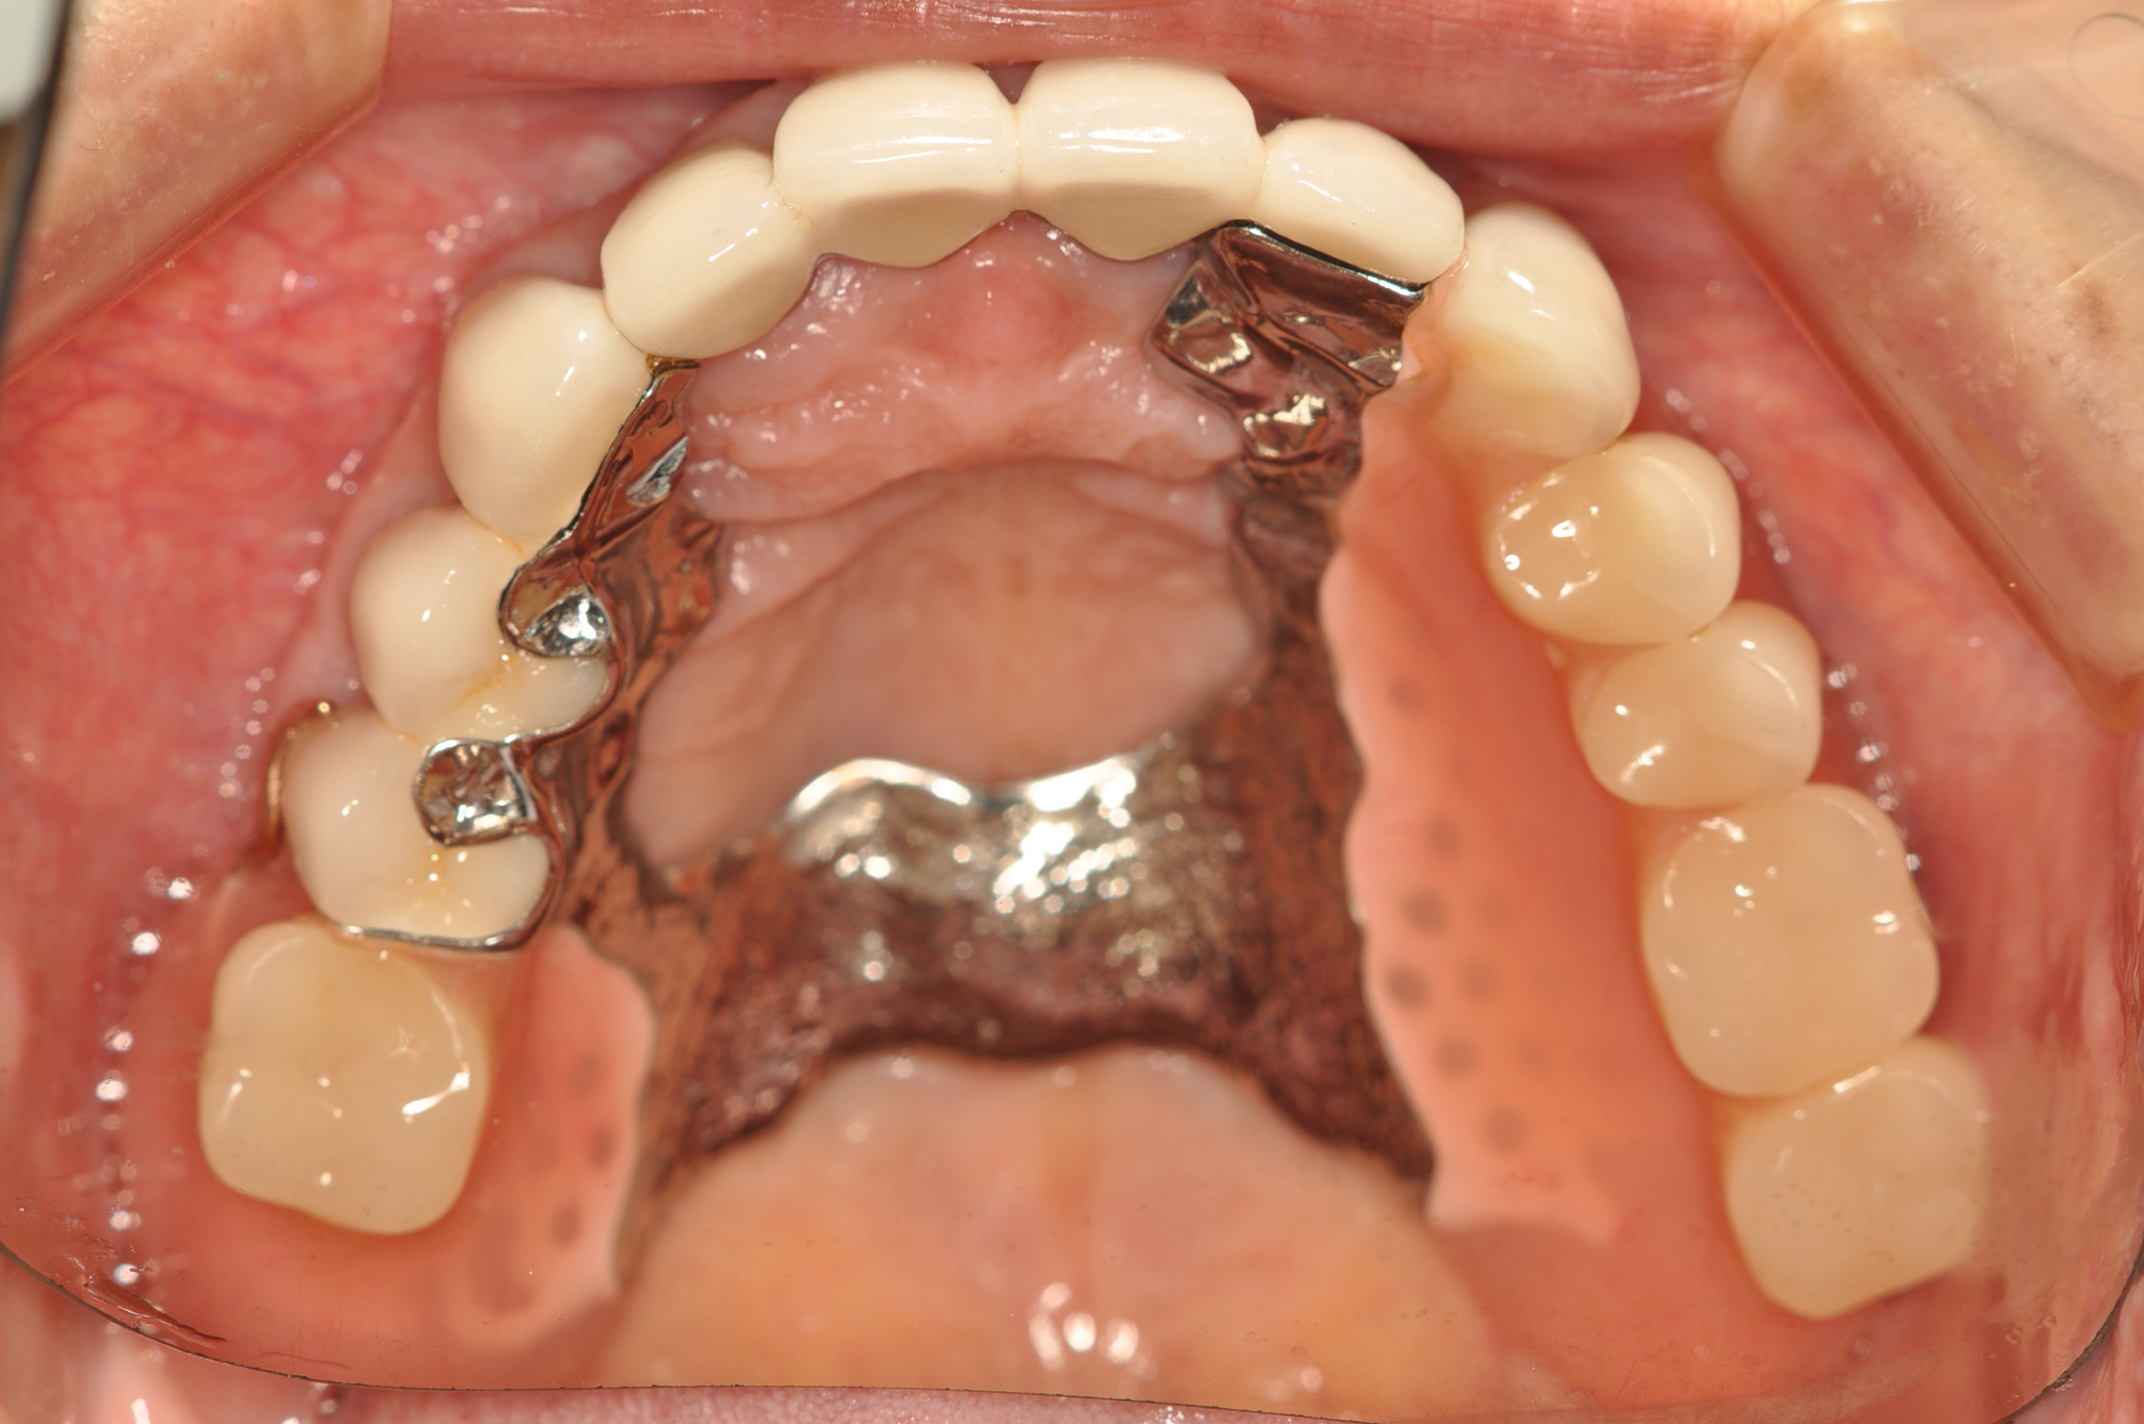

50代女性 部分義歯で対応した重度歯周病症例

娘さんがHPで安藤歯科を探していただいたそうです。義歯が入っているように見えない事が治療条件でした。

• BEFORE

盛岡 義歯 審美 歯周病

試適時の咬みわせチェックの写真です。装着時も咬合器にリマウントしてチェックします。